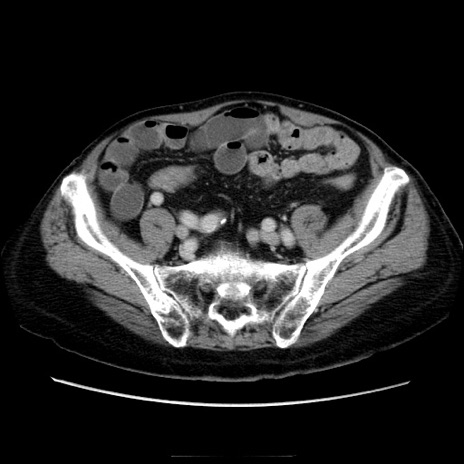

症例21(横断像)

【症例】70歳代男性

【主訴】腹痛

【現病歴】肝硬変・肝細胞癌にてかかりつけの方。約9時間前に食後より腹痛出現。症状が徐々に増悪し、嘔吐出現したため来院。

【既往歴】肝硬変、肝細胞癌(RFA、TACE後)

【身体所見】意識清明、表情苦悶様、BT 36℃、BP 129/78mmHg、P 88bpm、SpO2 97%(RA)、右上腹部から心窩部にかけて圧痛あり、反跳痛なし、筋性防御あり。

【データ】WBC 5800、CRP 0.16